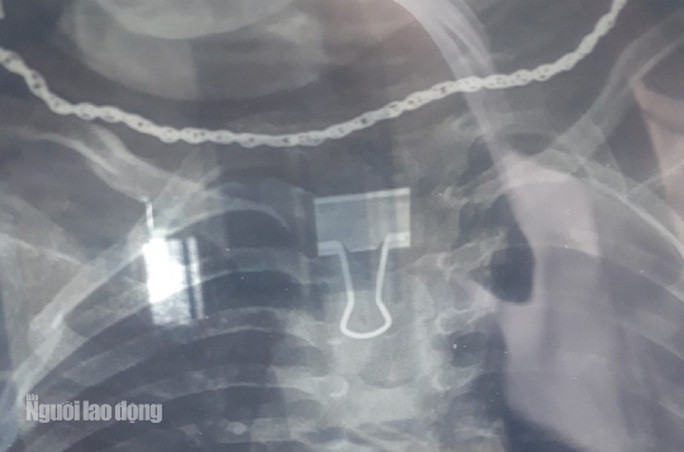

| Hình ảnh kẹp giấy trong thực quản bé 2 tuổi - Ảnh: Bệnh viện cung cấp. |

Tiến hành chụp X-quang các y, bác sĩ Bệnh viện Nhi Thanh Hóa phát hiện có dị vật kích thước 1x2 cm tại vị trí cách cung răng 13 cm. Niêm mạc thực quản tại vị trí dị vật phù nề xung huyết. Bệnh nhân được các bác sĩ can thiệp và gắp ra một kẹp giấy.